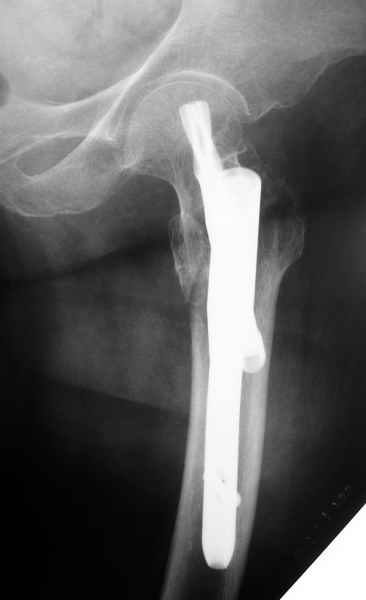

Второй случай тоже репозиция из малого доступа, больному 19 лет, множественные огнестрельные повреждениия конечностей, живота и черепа, правая конечность холодная, без пульсации. Ортопедический диагноз: огнестрельный перелом правого бедра. При срочной ангиографии повреждения сосудов не подтвердилось, конечность из-за ургентности состояния больного зафиксирована временным наружным фиксатором и больной оставлен на операционном столе для срочной лапаротомии хирургической службой.

Больной долго оставался нестабильным, только на 14 день удалось заменить на антеградный интромедуллярный штифт TFN (trochanteric femoral nail) SmithNephew. После неудачной попытки закрытой репозиции, несмотря на использование "joystick", проксимальный стержень от

наружного фиксатора, (перелом начал срастаться) репозицию провели из малого доступа, затем остальные этапы операции.

Случай был представлен из-за того, что больного оперировали после наружной фиксации и был риск инфекцирования через места проведения стержней (на снимках), прошло больше 3 месяцев, выписан из амбулаторной службы из-за отсутсвия надобности дальнейшего наблюдения.

Другие случаи: применение Synthes TTFN (trochanteric titanium femoral nail) и Blade Plate (угловая пластина), так что много различных вариантов фиксации подобных переломов.